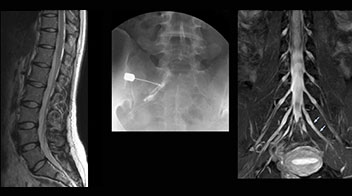

At Northern Fukushima Medical Center in Japan, excellent MRI visualization of nerves helps support confident diagnoses and informs surgical treatment decisions for patients with lower limb symptoms. MRI technologist Tanji and orthopedic surgeon Dr. Yabuki share how direct nerve visualization with the 3D NerveVIEW method adds information when diagnosing atypical herniations. The additional insights changed their way of working and benefit their patient care, as illustrated by some clinical examples.

“In such case, we would then browse through axial T2-weighted MR images slice by slice and mentally reconstruct the actual situation based on both radiculography and MRI. Fortunately, NerveVIEW can now very well show nerve courses and presence of nerve compression or edema in one single image series.” “We have often seen NerveVIEW directly depict details of the nerve compression that were not observed by radiculography. Therefore, we think that with NerveVIEW we can reduce the number of invasive examinations, especially for some patients with lumbar plexus symptoms.”

“Before NerveVIEW, diagnosis by MRI alone was sometimes difficult, unless there was a strong suspicion based on clinical symptoms,” says Shoji Yabuki, MD, DMSc, Orthopedic surgeon at Fukushima Medical University School of Medicine. “This is why we routinely perform selective lumbosacral radiculography (nerve root block) and x-ray in such cases. However, radiculography can only depict nerves as far as the contrast agent reaches. When a nerve is distorted by compression, the contrast agent will not pass through this compressed area, preventing us from evaluating the full nerve compression.”

“NerveVIEW is really useful for those cases where a nerve disorder is strongly suspected based on the clinical examination but our regular MRI images do not show any findings. These atypical herniations and spinal canal stenosis, occurring in 5% to 15% of the total lumbar herniation/stenosis cases are our main target when using NerveVIEW,” says Dr. Yabuki.